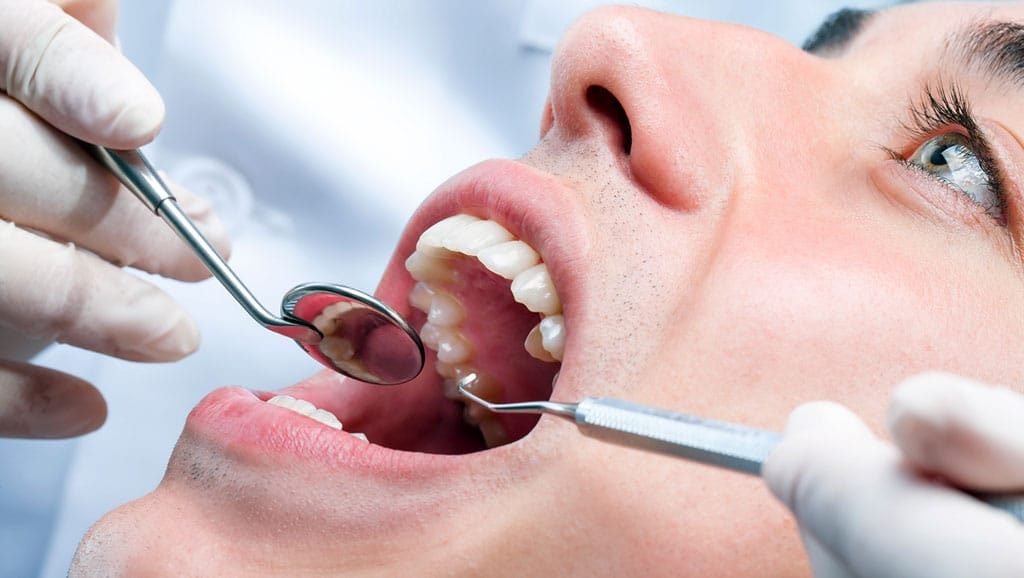

En Dental Life, ofrecemos una gama completa de tratamientos, desde prevención hasta estética dental. Nuestro equipo de especialistas y tecnología avanzada garantizan una atención personalizada según tus necesidades y objetivos.

En Dental Life cuidamos cada sonrisa con un enfoque integral. Ofrecemos tratamientos personalizados, realizados por especialistas altamente capacitados y con tecnología de última generación.

Tecnología de última generación

Contamos con equipos modernos que permiten diagnósticos más precisos y tratamientos más efectivos, rápidos y menos invasivos.